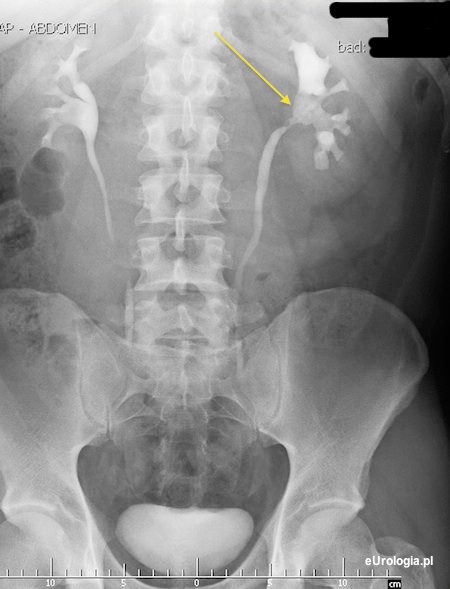

Kamica odlewowa nerki